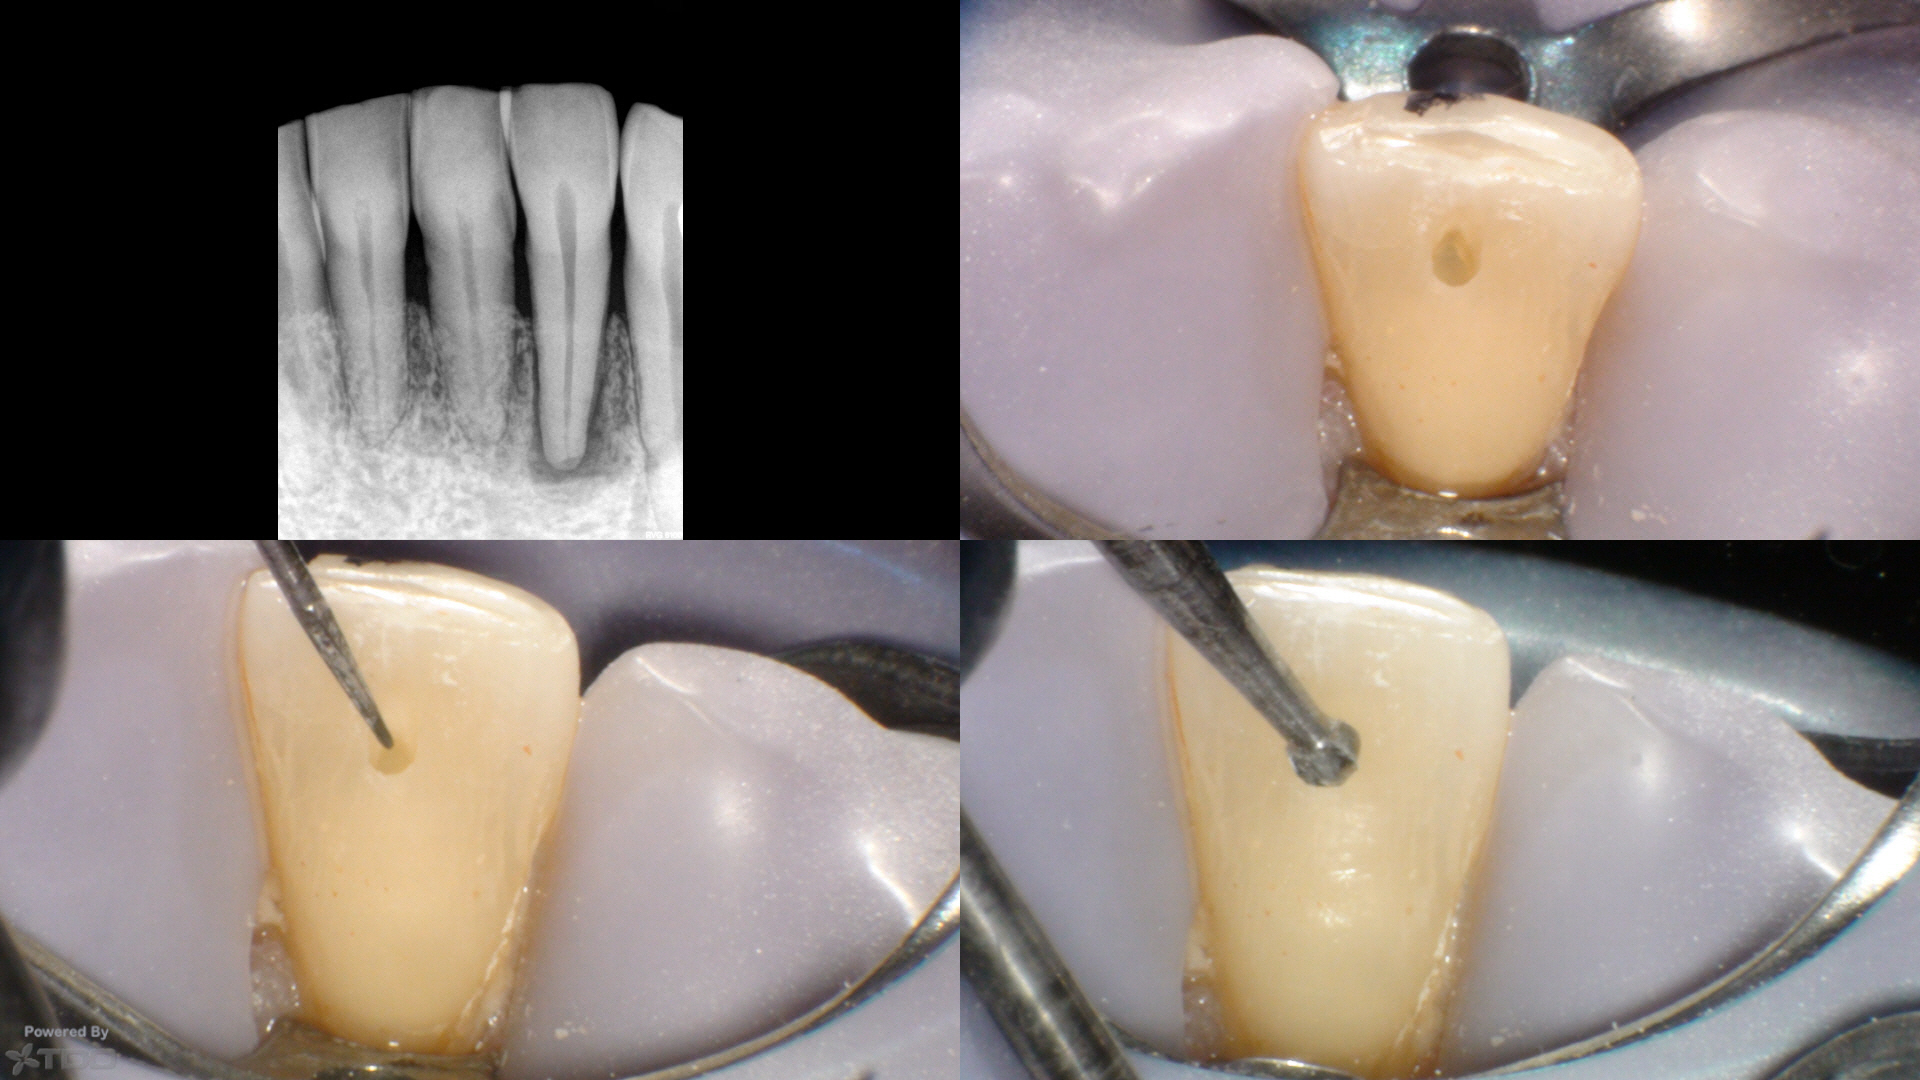

Four year followup.

Look at this case carefully and consider:

What are the chances that this tooth breaks 20 years from now? And since tooth failure on endodontically treated teeth is more related to tooth fracture than endodontic failure—-isn’t this patient far better off with this minimized approach than your typical search and destroy approach?